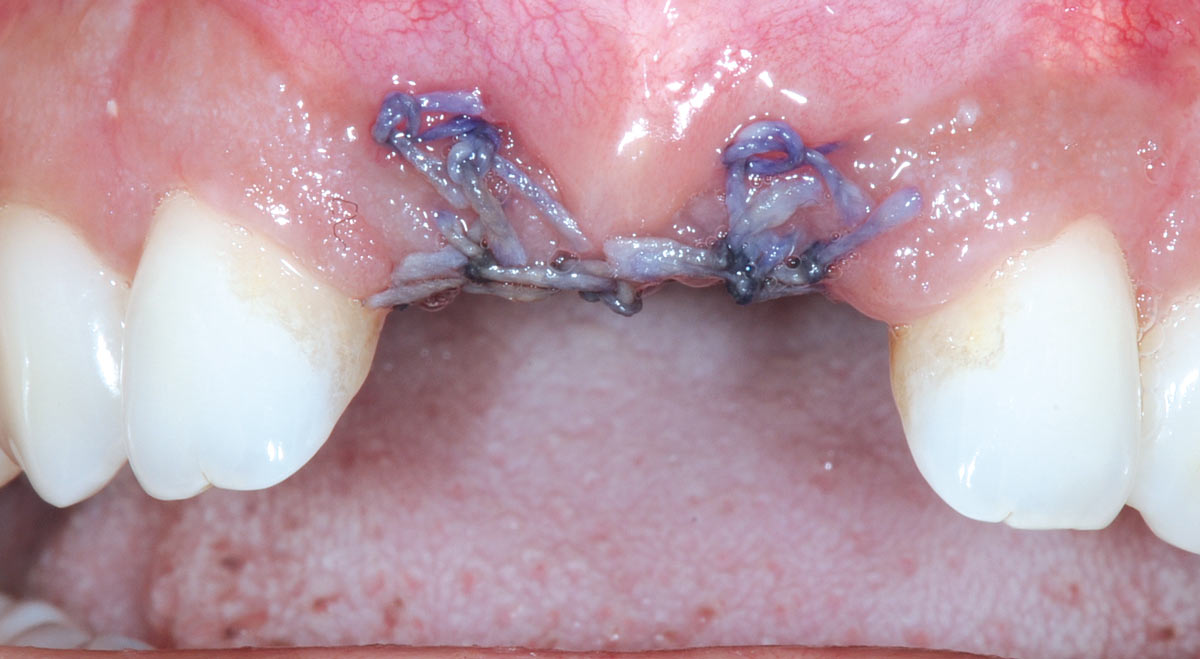

17/26 - Mattress sutures to stabilize the graftBone augmentation in aesthetic zone with maxgraft® bonering - Dr. A. Patel

18/26 - Sutured free of tension with vycrilBone augmentation in aesthetic zone with maxgraft® bonering - Dr. A. Patel